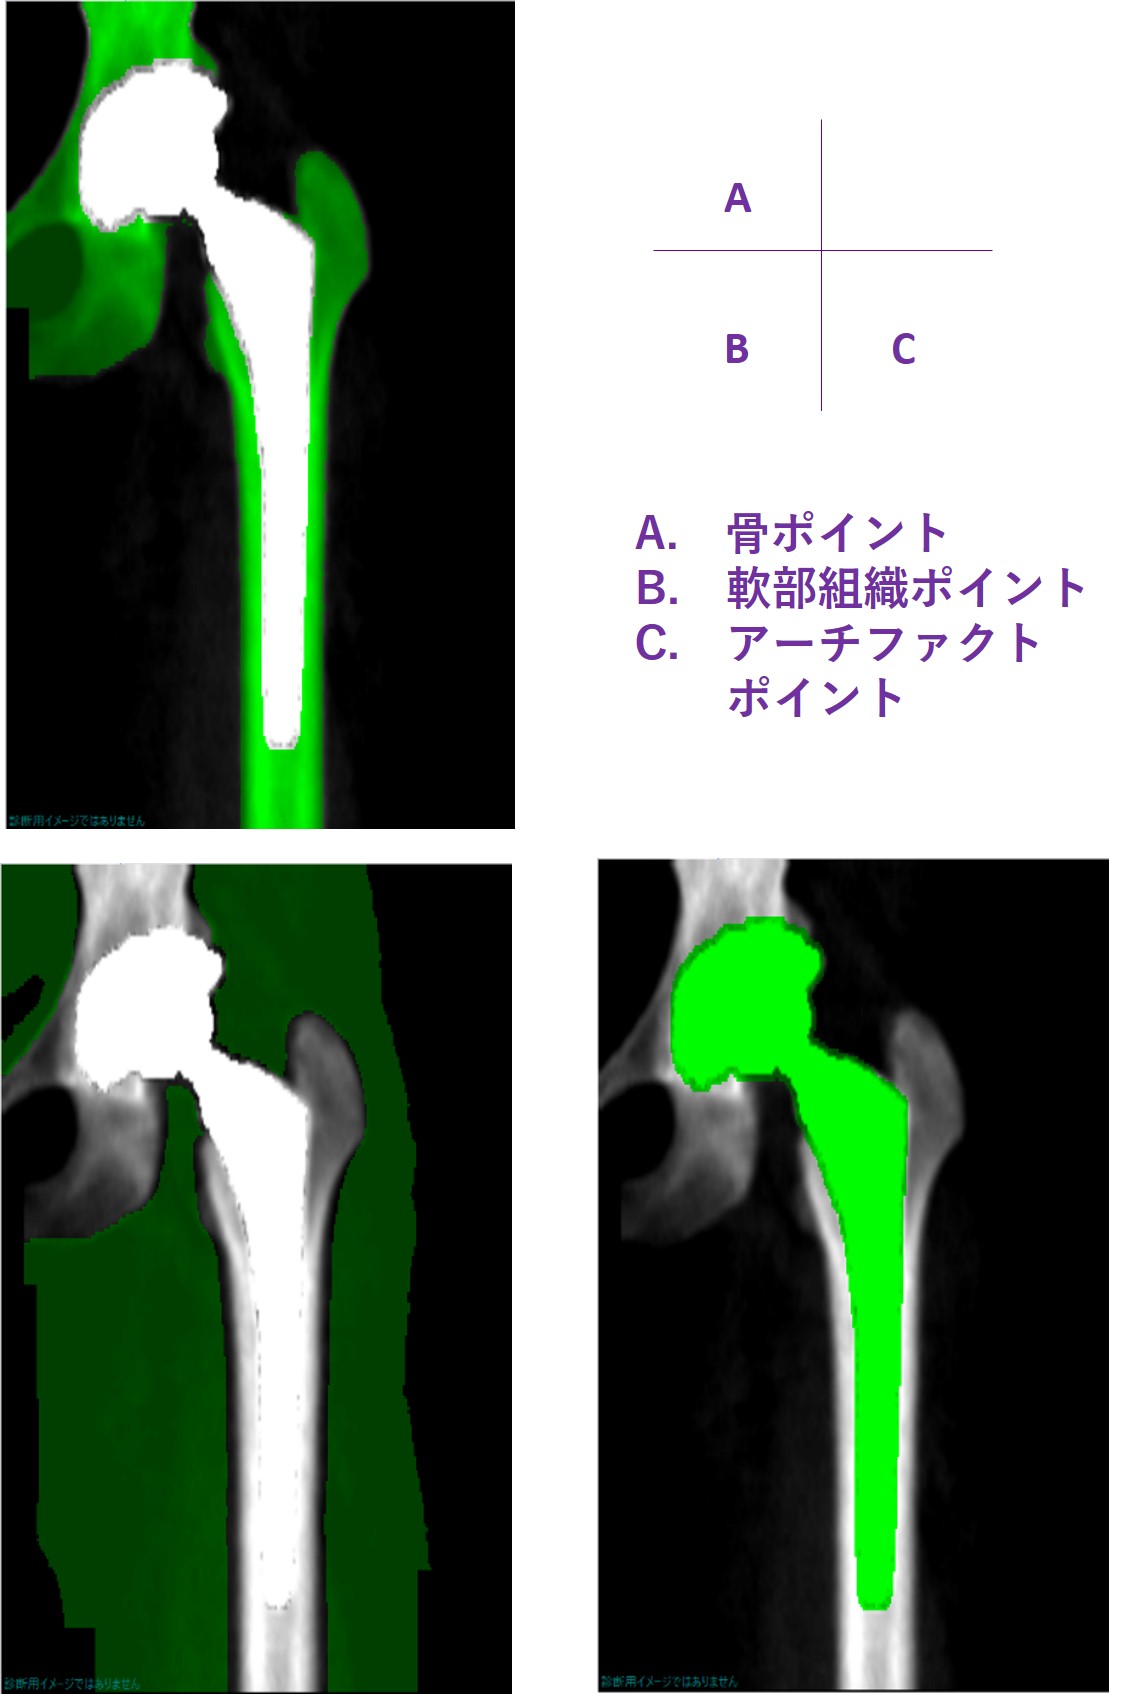

まず、すべてのピクセルに関して自動的にポイントタイプ(ピクセルの仕分け分類)を行います(図3)。その際、特に重要なポイントは、骨領域、軟部組織領域、そしてアーチファクト領域です。このソフトウェアの場合、いかに正確にアーチファクトを認識して、計算する部分から除外するかが重要となります。

図 3.